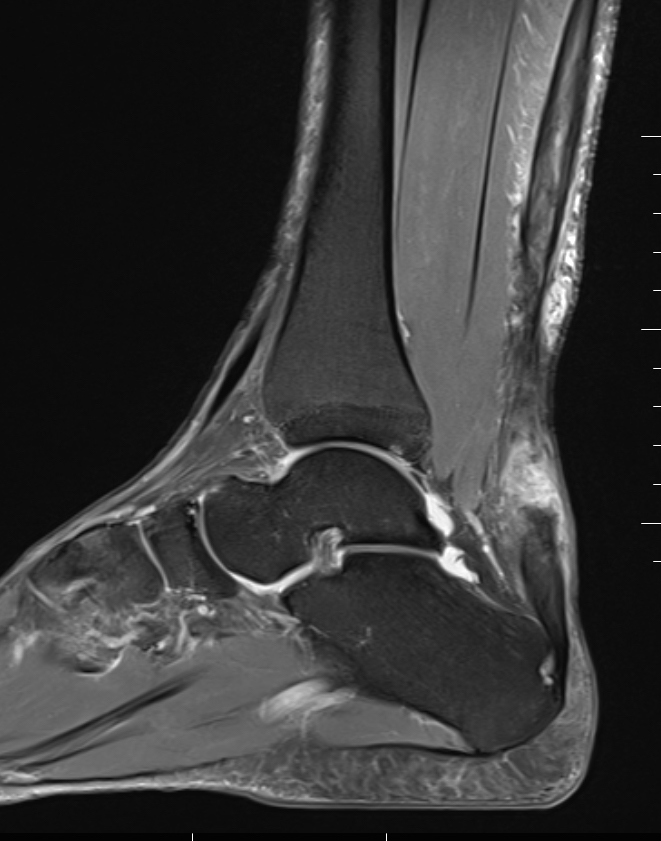

MRI

Indication

- incomplete rupture / clinical uncertainty

- chronic tears - measurement of gap for reconstruction planning

Acute

High grade partial thickness